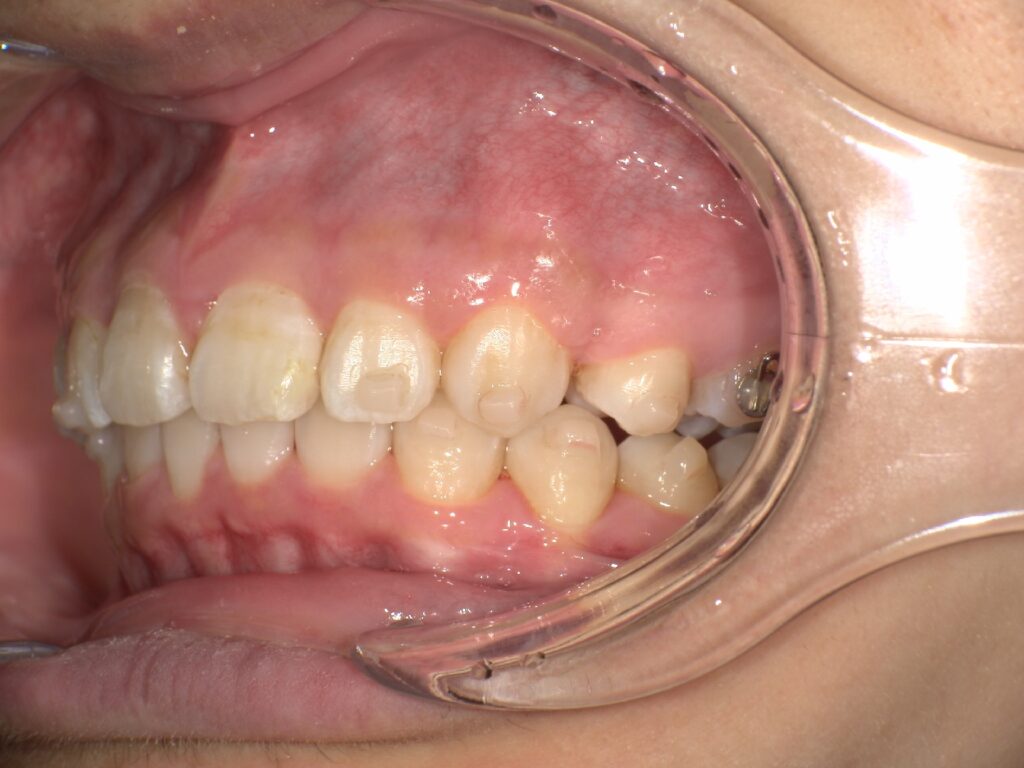

下記のケースでは、奥歯の噛み合わせが悪くなかったことから、患者様の希望もあり、部分矯正で対応いたしました。

上顎の前歯が大きく突出しています

明らかに前歯の突出感が改善し、患者様はこの時点でとても喜ばれていました

矯正治療終了時 部分矯正ということもあり、短期間で矯正治療を終了することができました